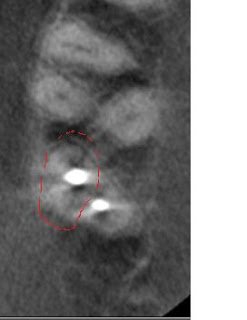

In the below left image, I circled the missed DB canal. The below right images (one is reversed, please forgive me) display the missed DB root in the sagittal plane as well as the apical perforation and over enlargement (strip perforation) of the MB root.

The below horizontal slice displays the previous instrumentation into the furcation between the MB and DB roots. I question if the radiolucent line mesial to the radiopacity is a fracture.